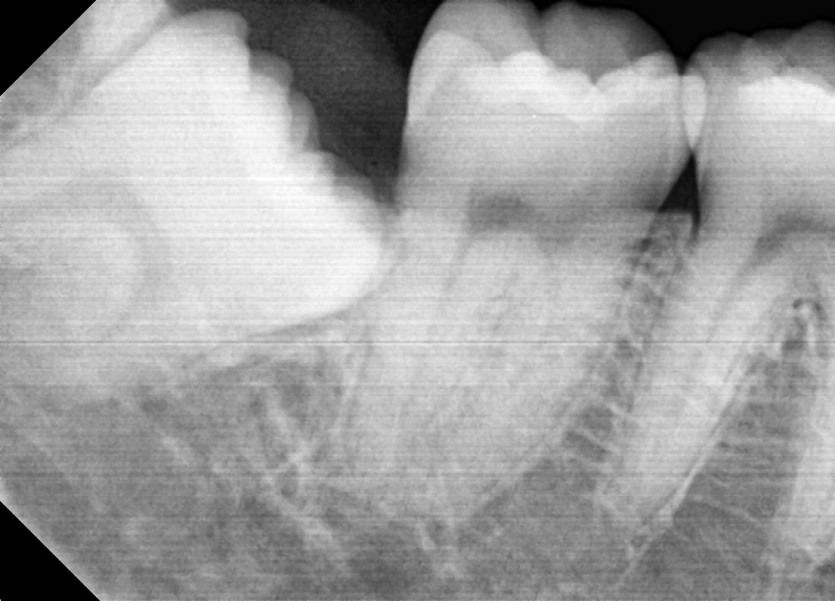

#18,48 사랑니 발치

구강외과 전문의가 당일 발치했습니다.